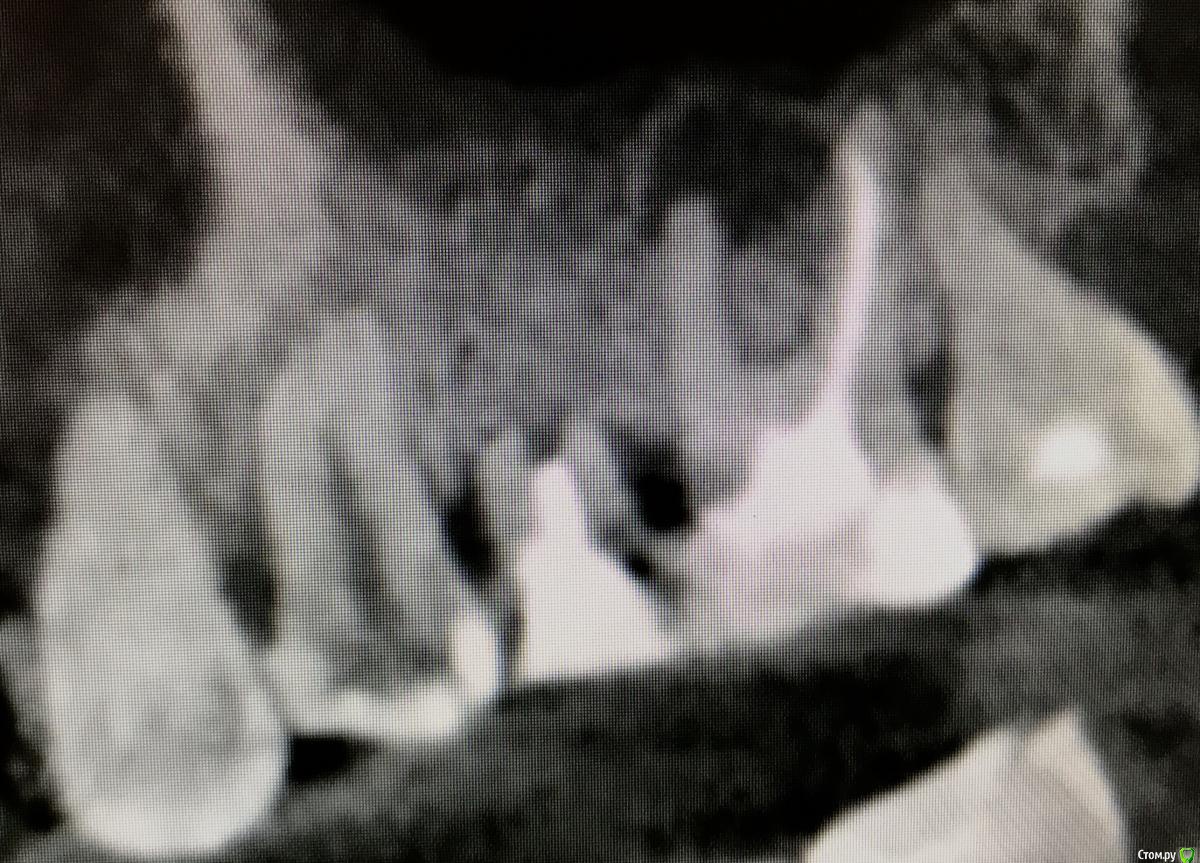

kamranchick Опубликовано 22 апреля, 2018 Поделиться Опубликовано 22 апреля, 2018 Камран, попробуй и узнаешь)))Дык у меня много работ таких на данный момент))) просто пока не раскрывал))))вот из последних) 3 Ссылка на комментарий

kamranchick Опубликовано 30 мая, 2018 Поделиться Опубликовано 30 мая, 2018 Реколы первые 1 Ссылка на комментарий

АнтонТЛТ Опубликовано 30 мая, 2018 Поделиться Опубликовано 30 мая, 2018 (изменено) Чет как-то не ахти. Как думаешь в чем причина? Пробки неподвижны? Изменено 30 мая, 2018 пользователем АнтонТЛТ Ссылка на комментарий

kamranchick Опубликовано 30 мая, 2018 Поделиться Опубликовано 30 мая, 2018 Чет как-то не ахти. Как думаешь в чем причина? Пробки неподвижны?Пробки намертво приклеены.Причина не знаю в чем(Это провал, ибо пациент готовится на имплантацию уже.Тут даже 3.5 с трудом проходит 1 Ссылка на комментарий